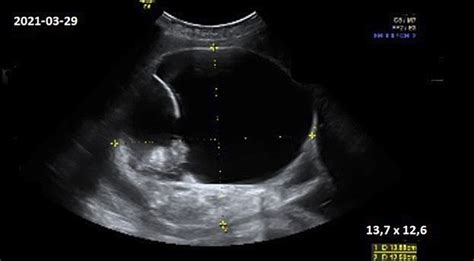

20-22 savaitę atliekamas svarbus ultragarsas, kurio metu galima aptikti rimtų vaisiaus vystymosi sutrikimų.